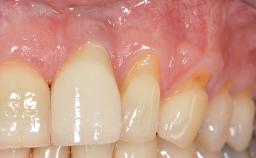

A 30-year-old woman was referred by her general dentist for evaluation of an esthetic complication related to previous implant treatment for congenitally missing maxillary lateral incisors. The patient’s chief complaint was the inadequate esthetic appearance of her smile. The case demonstrates the use of a combined approach to achieve optimal results. Two different flap designs - a tunnel technique and a coronally advanced flap - are employed based on the surgical objectives for the affected site.

Lip Line No exposure of papillae Exposure of papillae Full exposure of mucosa margin

Periodontal Phenotype Low-scalloped, thick Medium-scalloped, medium-thick High-scalloped, thin